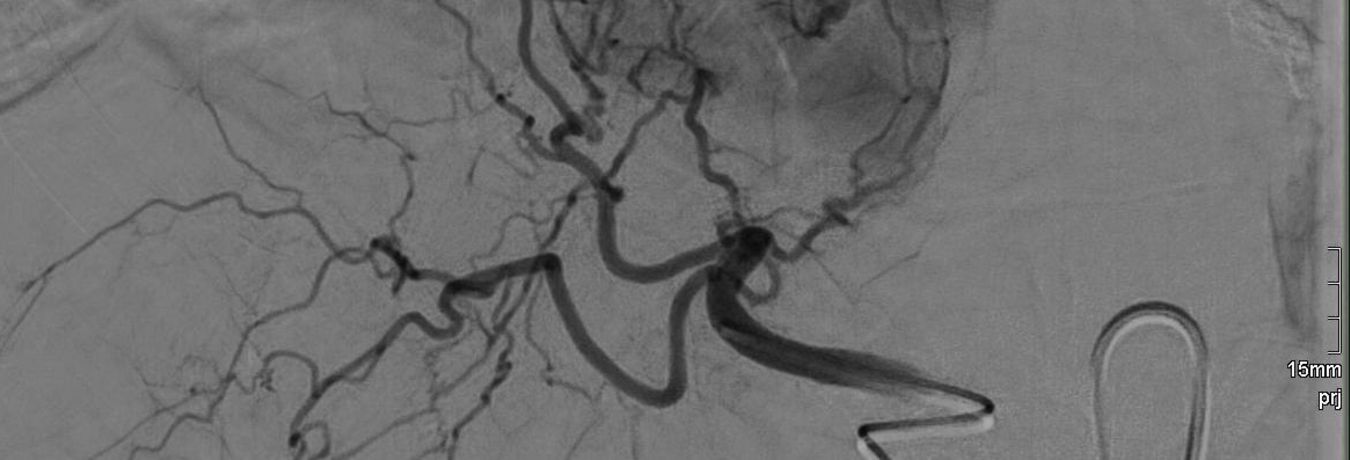

Hierzu wird unter Durchleuchtung ein dünner Katheter, welcher über die Leistenschlagader eingebracht wird, bis in die Leber vorgeschoben. Über diesen Katheter werden anschließend kleinste Partikel, sogenannte Mikropartikel, direkt in die Gefäße gespritzt, welche einen Lebertumor versorgen. Dadurch wird zum einen die Blutversorgung des Tumors verringert, da die Gefäße durch die Partikel verstopfen. Zum anderen wird das Zellwachstum im Tumor gehemmt, da die Mikropartikel mit einem Chemotherapeutikum beladen sind, welches seine Wirkung direkt im Tumor entfalten kann, ohne sich wie bei einer „normalen“ Chemotherapie im ganzen Körper zu verteilen.

Ähnlich wie bei der TACE wird bei der SIRT (selektive interne Radiotherapie) ein dünner Katheter über die Leistenschlagader bis in die Leber vorgebracht. Hier werden nun über diesen Katheter Mikropartikel in die zum Tumor führenden Gefäße gespritzt, welche mit einer radioaktiven Substanz beladen sind. Im Tumor entfaltet die abgegebene radioaktive Strahlung ihre Wirkung und führt zum Untergang der Tumorzellen, wohingegen das gesunde Gewebe aufgrund der geringen Reichweite der Strahlung weitestgehend geschont wird. Im Gegensatz zur Strahlentherapie „von außen“, also der klassischen Bestrahlung, kann bei der SIRT eine höhere und effektivere Strahlendosis direkt im Tumor verabreicht werden.